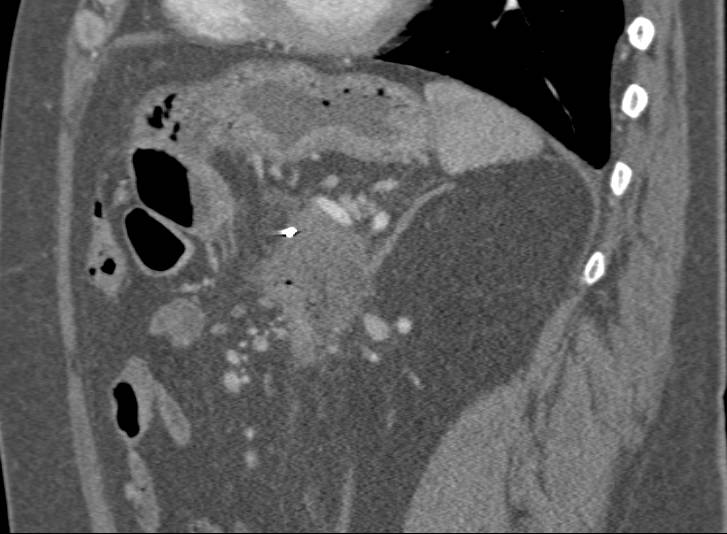

Mucinous Cystic Neoplasm (MCN) in Tail of the Pancreas